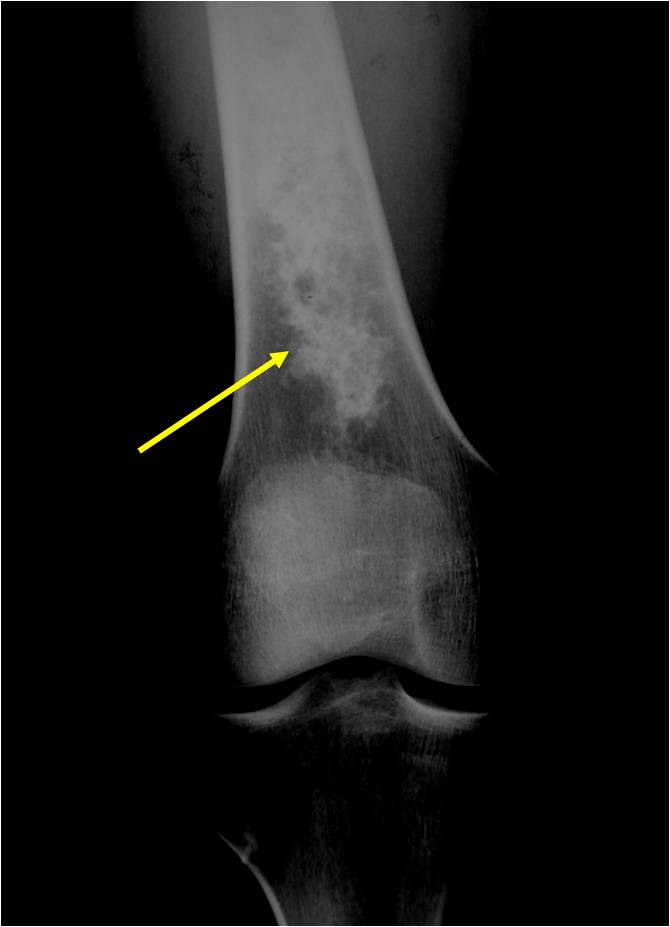

- Localized, radiolucent defect usually with punctate calcifications

- Calcifications are typical but not always present

- Matrix may demonstrate various degrees of calcification

- Calcifications are stippled, punctate, popcorn like calcifications and “Ring and Arc” calcifications

- Cortex may be scalloped and thinned in the phalanges

Plain X-Ray:

- Geographic lytic lesion

- Central often metaphyseal in long bones

- Expansile remodeling with thinned cortex

- Chondroid matrix with calcifications in majority of tumors

- Approximately 20% have limited or no calcifications

- Features consistent with chondrosarcoma

- Pain attributable to lesion

- Age greater than 50

- Cortical destruction and a soft tissue mass

- Periosteal reaction and thickening

- Endosteal erosion>2/3 cortical thickness on a CT scan

- Size greater than 5 cm